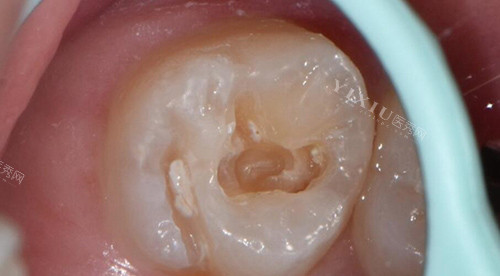

像龋坏较浅时,采用光固化树脂进行填充补牙,这种材料性能比较稳定、美观,但如果龋坏面较大较深,用它来补牙,就可能因为无法非常好地贴合较大的龋洞,而导致材料容易脱落。

当牙齿龋坏面较大较深,但还未伤及牙根时,用树脂补牙材料容易脱落,此时更推荐全瓷嵌体补牙。

补完后边缘密合性更好,很少出现牙体敏感、边缘微渗漏的情况,补牙材料也不易脱落。全瓷嵌体美观,长期结果较好,可以延长牙齿的使用寿命,并且使牙齿修复到一定的硬度。